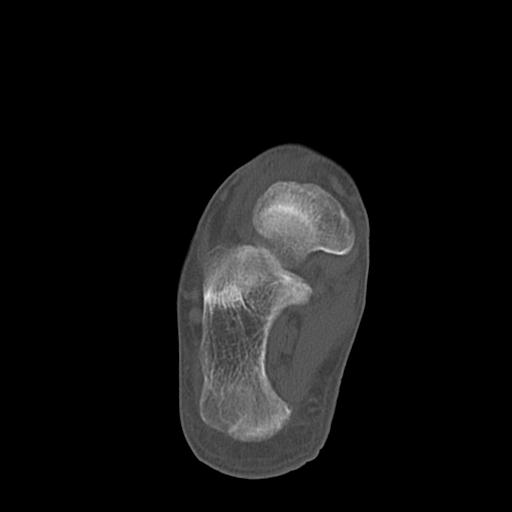

102755 1/4 2R 1/15 2R 右足関節 68歳女性 右三果脱臼骨折